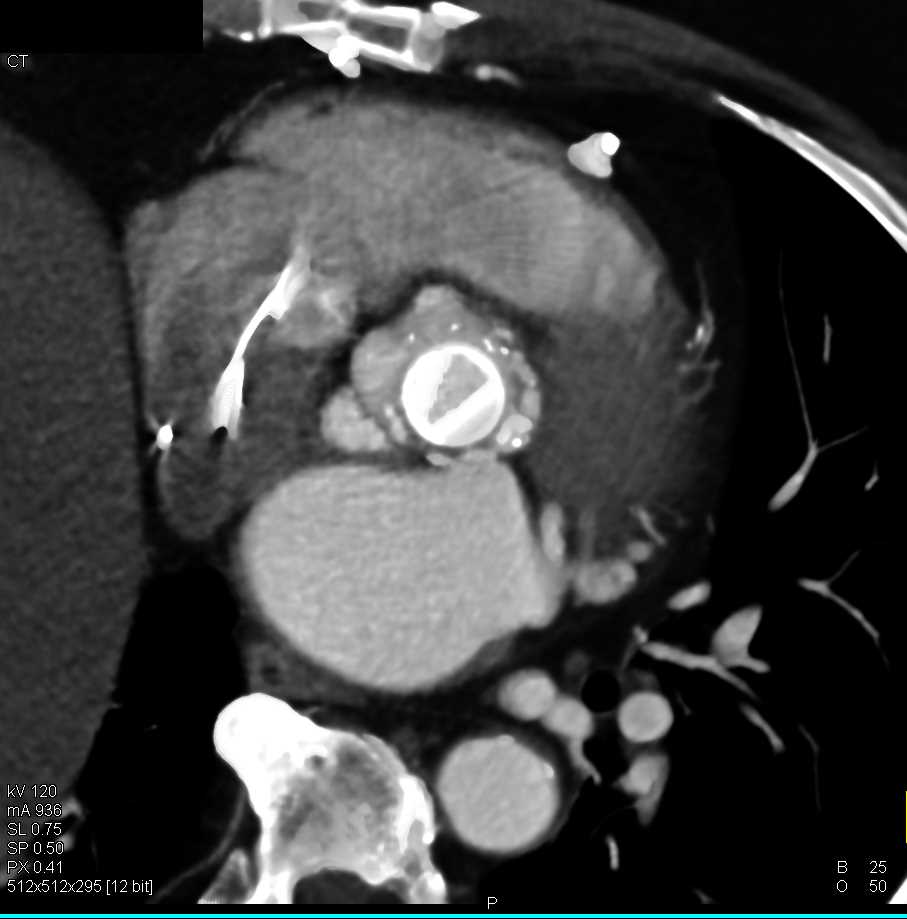

Pseudoclot in the Left Atrial Appendage